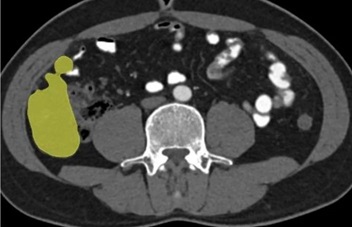

阿梵D胃肠疾病(结肠癌)临床案例分享

↑胃肠病灶切除分析

腹腔肿瘤包括肝肿瘤、脾肿瘤、肠系膜肿瘤等。三维重建技术在腹腔肿瘤的诊断、治疗和预后评估中具有重要作用。通过三维重建,可以更全面地展示肿瘤的位置、形态、侵犯范围以及与周围器官的关系,有助于医生制定更精确的手术方案和预后判断。此外,三维重建还可以用于评估手术效果和指导进一步的治疗,例如在机器人辅助手术中,三维重建技术可以提供更精确的手术导航和操作指导。